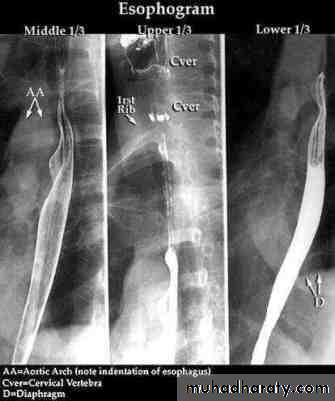

Investigations Chest X-ray; widening of the mediastinum, aspiration pneumonia.A barium swallow; tapered narrowing of the lower esophagus, esophageal body is dilated, aperistaltic and food-filled.Endoscopy; must always be carried out, carcinoma of the cardia can mimic the presentation and radiological and manometric features of achalasia ('pseudo-achalasia').Manometry; confirms the high-pressure, non-relaxing lower esophageal sphincter with poor contractility of the esophageal body.